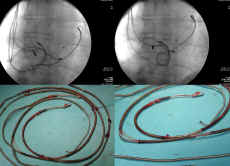

silikonową. Wg naszych wieloletnich badań, zjawisko

przetarcia osłonki silikonowej z odsłonięciem spirali

(czyli perforacją osłonki zewnętrznej) obserwuje się u

ok. 25% pacjentów, u których usunięto elektrody z różnych

przyczyn (50% to wskazania infekcyjne). I co ważniejsze -

- Okoliczności występowania. Każdy, kto wymienia

morfologicznym przetarcia występują w układzie żylnym,

a przede wszystkim w obrębie prawego serca. Niezależnymi

czynnikami zwiększającymi prawdopodobieństwo wystąpienia

przetarcia są: wiek i liczba elektrod w układzie

sercowo-naczyniowym, obecność w układzie elektrody

wchodzącej do zatoki wieńcowej oraz obecność zbędnych

nieprawidłowych pętli w prawym przedsionku bądź prawej

komorze. Czyli czas i wzajemny kontakt poruszających się

w różnych kierunkach elektrod mają znaczenie decydujące.